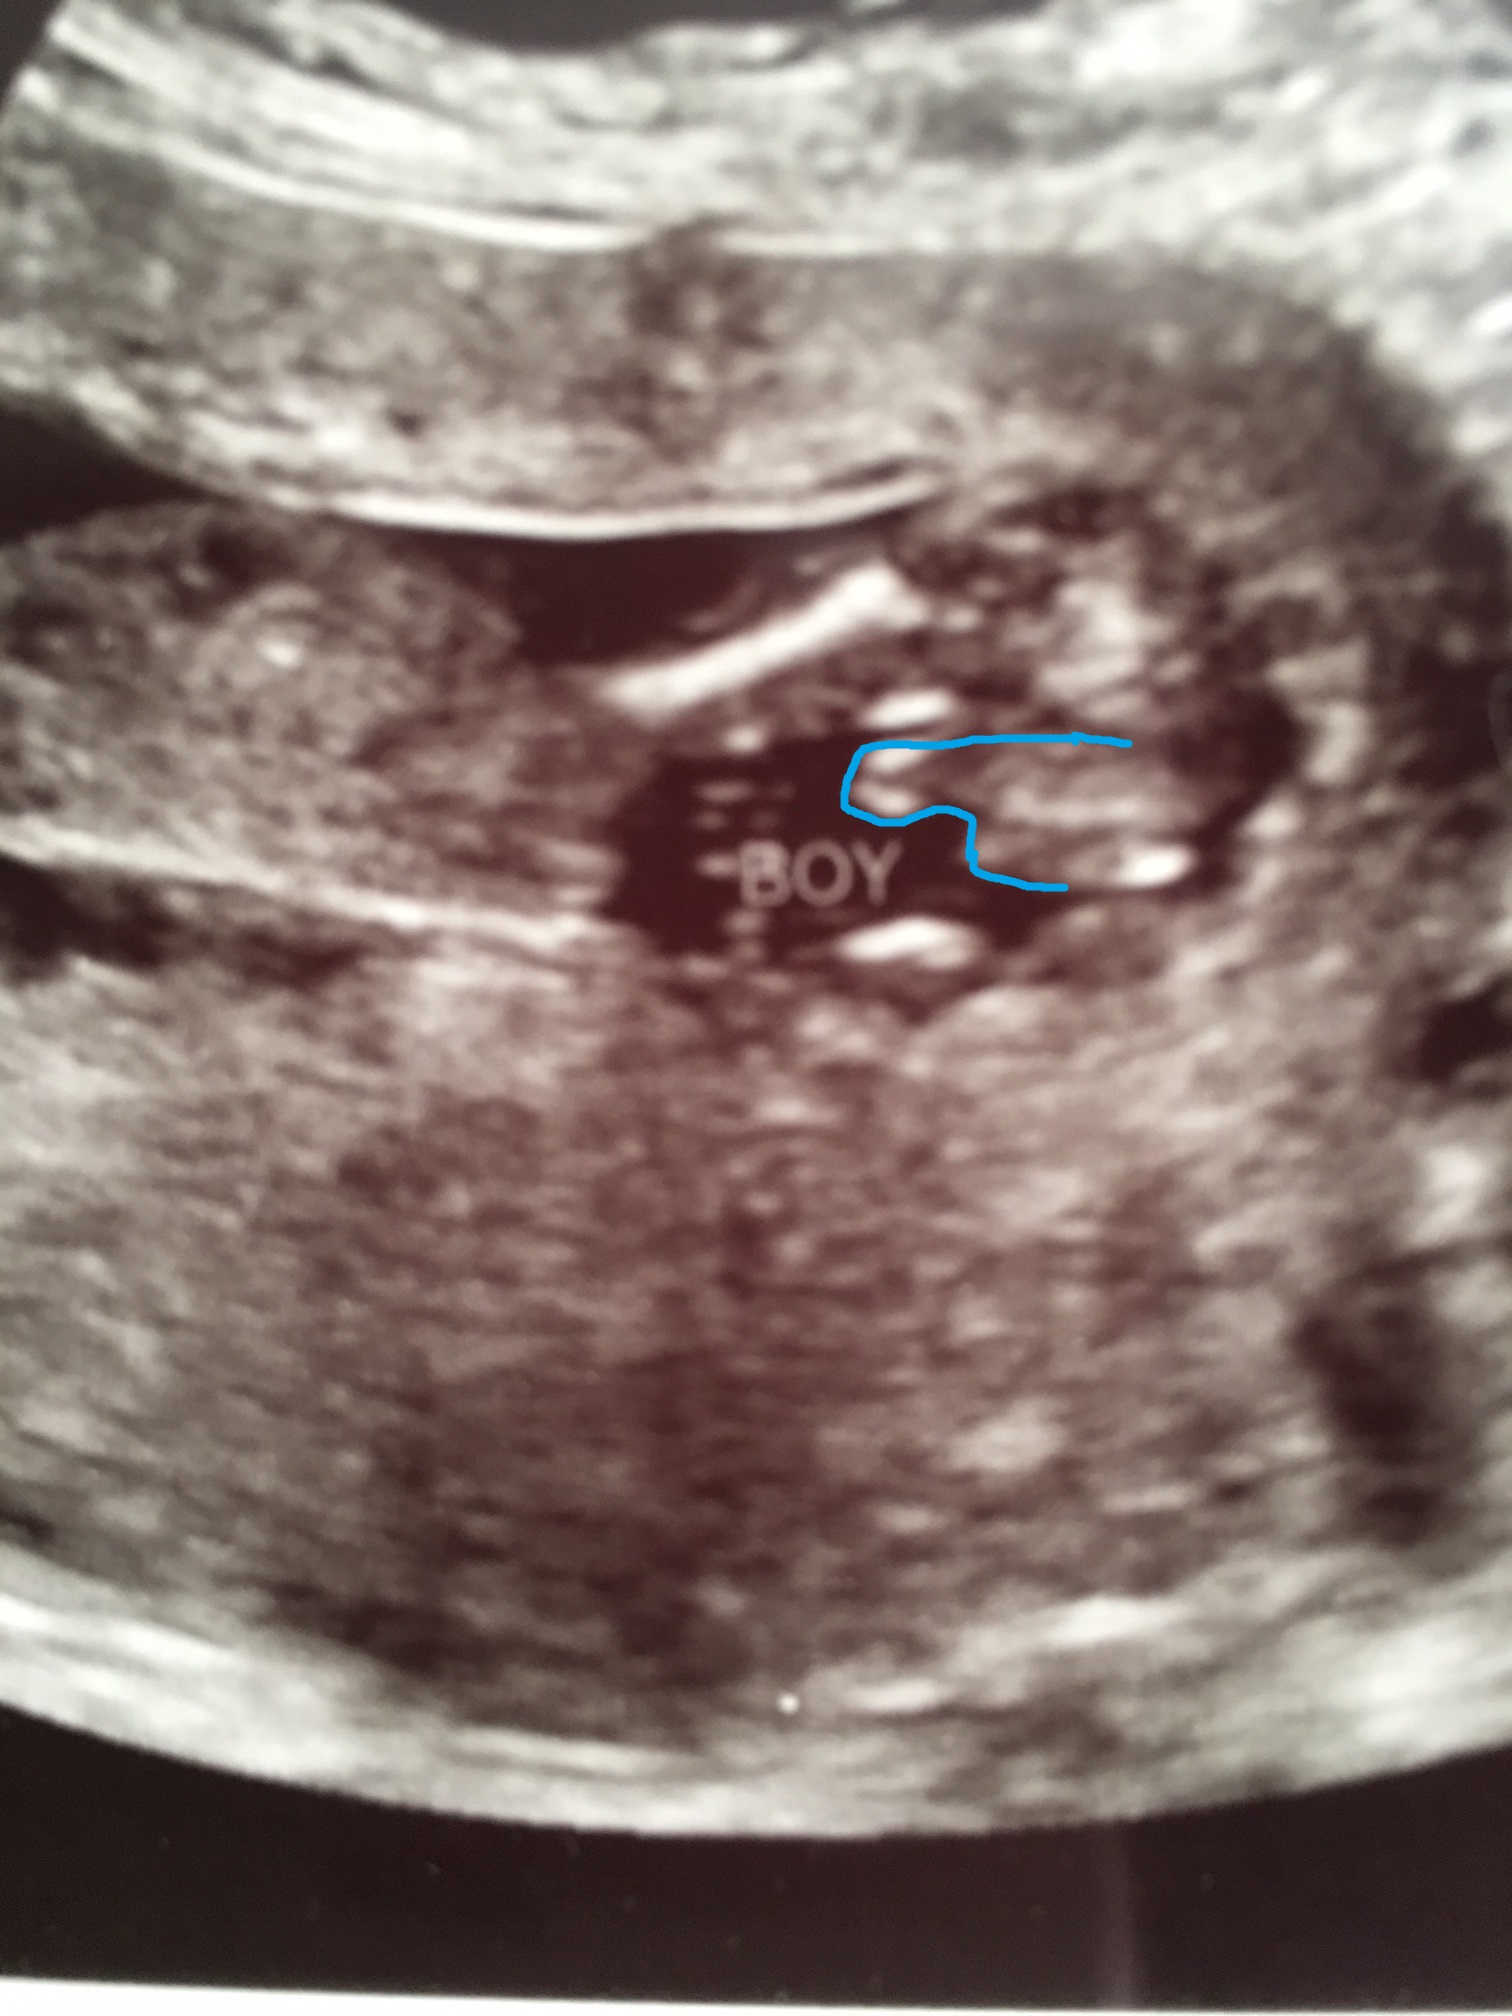

Does this really look like a boy to you?

Really bad potty shot, I can't figure it out. Maybe like this? :

Boy[emoji170]